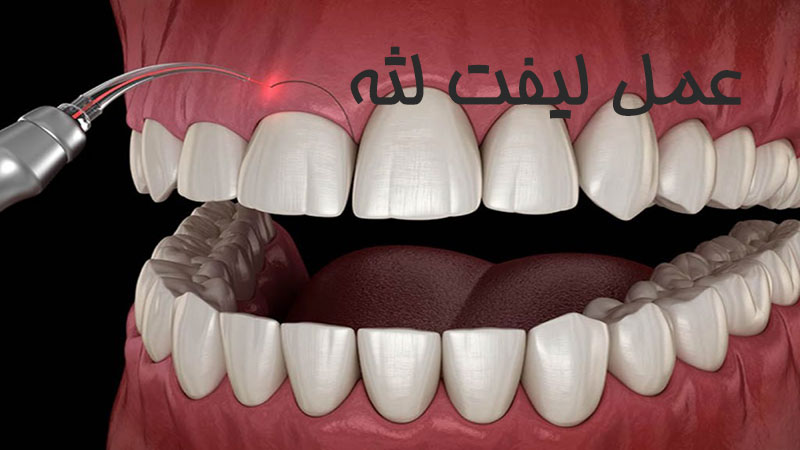

لیفت لثه بدون جراحی

ممکن است پزشک ترجیح دهد روش جراحی لیفت لثه با لیزر را امتحان کند. به این ترتیب، اول با بی حسی موضعی شما را از دردهای معمول در فرایند درمان راحت می کند و بعد با لیزر بافت شل و بیمار لثه را بر می دارد. در این مرحله یک بتونه به صورت موقت روی خط لثه شما می گذارد تا در طول درمان لثه راحت تر غذاها و نوشیدنی های سرد و گرم را مصرف کنید. به این شکل تقریبا لیفت لثه بدون جراحی به پایان می رسد. وقتی اثر داروی بی حسی رفت می توانید به کار و زندگی تان برسید. چند هفته بعد هم کانتور با شکل لثه شما منطبق می شود و خوبِ خوب می شوید. ساده و بی دردسر!